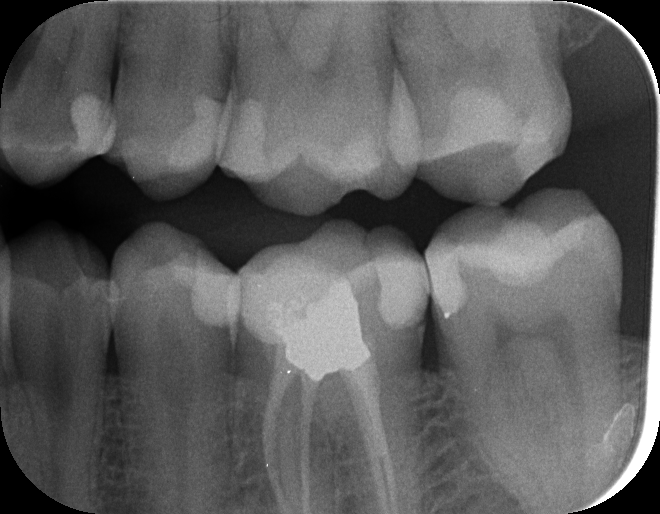

Scheinbar tiefes Loch das demnächst eine Füllung bekommt. Ist das erkennbar wenn ja wo?

18er oberer rechter Weißheitszahn bereits 2 Füllungen. Loch sehr groß.

Entscheidung heute: Extraktion, vor weiterer Füllung, da diese vermutlich bis zu Nerv geht.

Und tatsächlich der Extrahierte Zahn zeigt die Tiefe des Loches bis zum Nerv.

=> Gute Entscheidung den zu extrahieren.